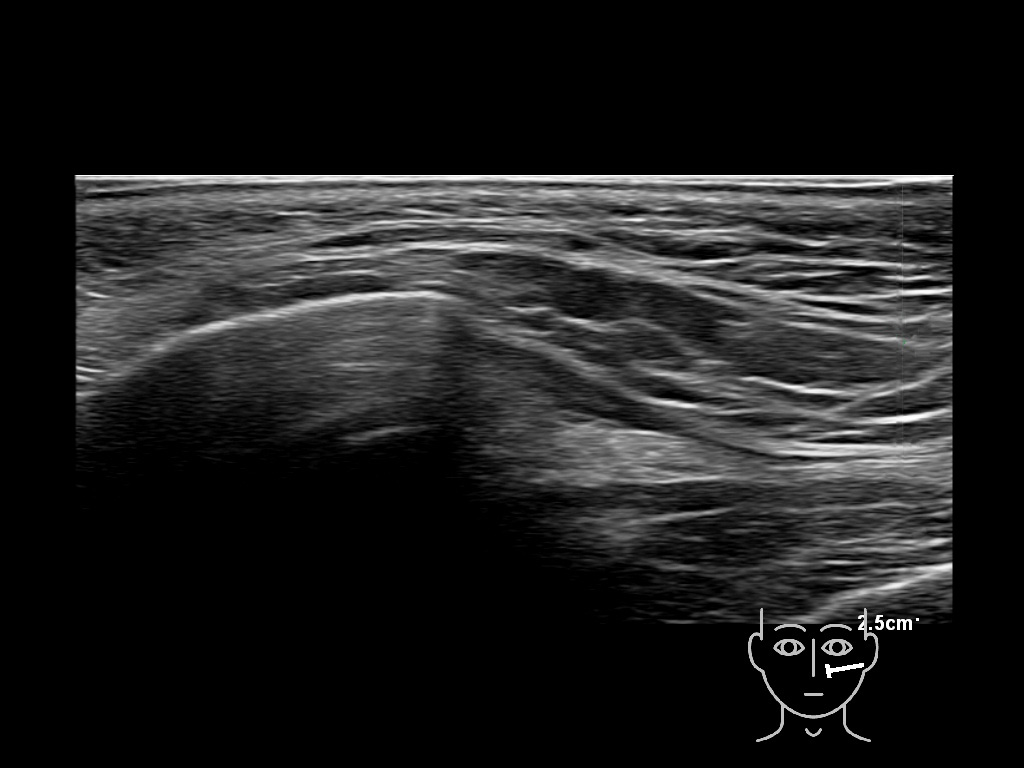

Filler behavior - Temple zygoma US

Study the first image to recognize the different layers. If you are sure about the layers, swipe to the second image to view the answer (if applicable).